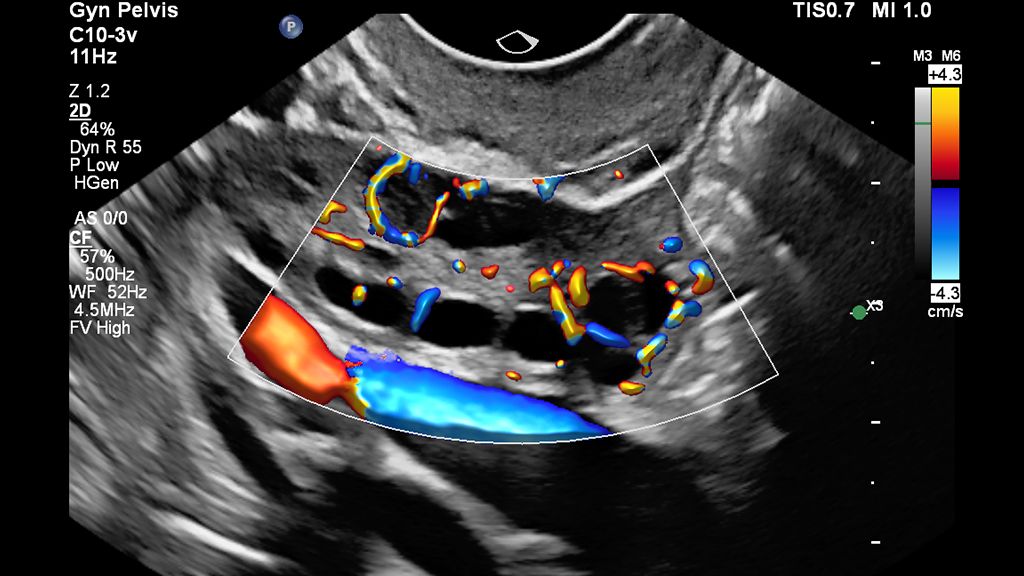

• MicroFlow HD detects low-volume, low-velocity blood flow in uterine and ovarian vasculature with high resolution, minimal artifacts and a high frame rate.

• Clinical image of pelvis scanned with MFI HD using EPIQ Elite and C10-3v transducer

MFI HD with Flow Viewer image of the ovary

• Clinical Color Flow image of ovary scanned with Flow Viewer on EPIQ Elite

Color Flow with Flow Viewer image of the ovary